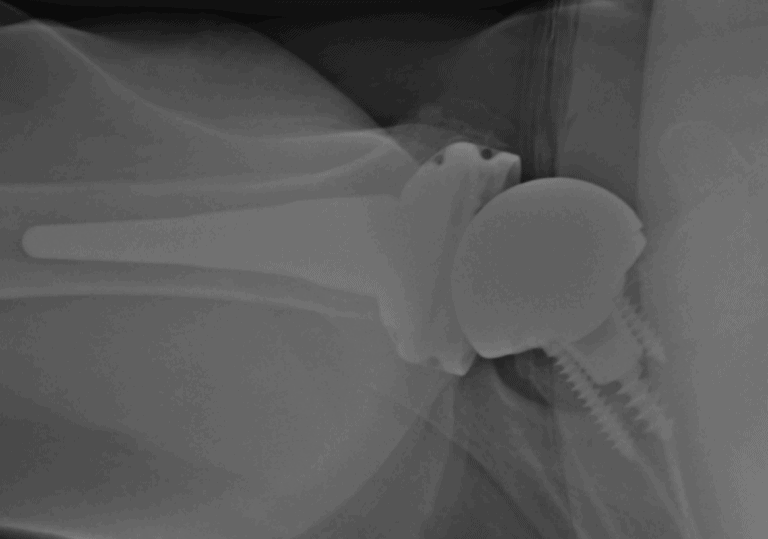

Arthrex, Convertible Universal Baseplate